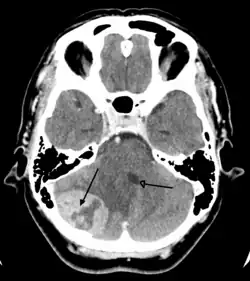

![]() | |

| Brain metastasis in the right cerebral hemisphere from lung cancer, shown on magnetic resonance imaging | |